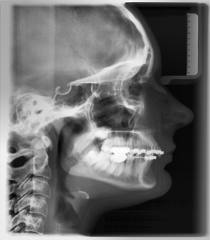

Ukoliko se odlučite da kod nas nastavite sa terapijom, dijagnostika mora da se dopuni uzimanjem otisaka za studijske modele, fotografisanjem lica i zuba i još jednim rendgenskim snimkom-profilnim snimkom glave. Na osnovu otisaka, dobijaju se gipsani studijski modeli-replika vaših zubnih lukova. Na tim modelima ortodont vrši precizna merenja i tako dolazi do tačne dijagnoze i mogućnosti za terapijsku proceduru.

Na osnovu sprovedene anamneze, kliničkog i funkcionalnog ispitivanja, analize rendgenskih snimaka, studijskih modela i fotografija, ortodont dobija sve relevantne podatke o ortodontskom problemu jednog pacijenta. Sve te podatke on sklapa u jedinstvenu dijagnozu i odlučuje koji terapijski postupak je najbolji za datog pacijenta.